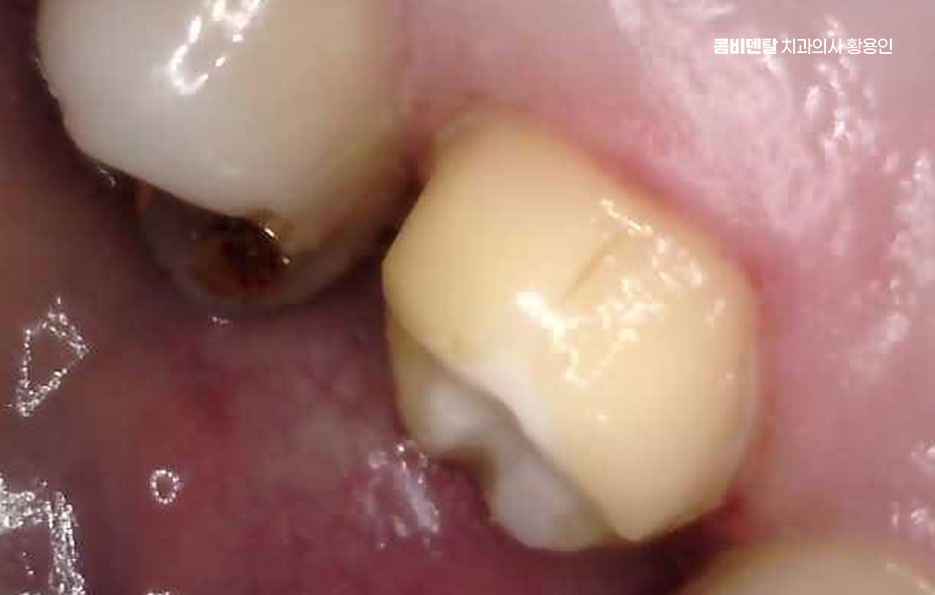

인레이 치료 후 통증 두 번째 원인으로는 인레이와 주변 치아 사이의 틈이 발생한 경우로 처음 치료할 당시에는 인레이가 정확히 맞았더라도 시간이 지나면서 치아는 미세하게 마모되거나 잇몸이 내려가고, 인레이의 치아 사이 경계 부위가 어긋나면서 틈이 생긴 경우로 쉽게 말해 인접면 충치가 발생한 경우도 있는데 이 틈은 충치뿐 아니라 치주염이나 이물감, 시림으로도 이어질 수 있으며 잇몸 자극이 생기기도 하고, 인접 치아 사이에서 음식물이 자주 끼게 되는 문제도 발생할 수 있어요

또 인레이 치료 후 통증이 주로 잇몸 쪽에서 통증이 느껴지는 경우에는 단순히 인레이의 문제가 아니라, 치아 주변의 치주조직에 염증이 생겼을 가능성도 있어요. 인레이 치료 후 오랜 시간이 지났을 때, 특히 위생 관리가 어려운 위치의 치아라면 치석이 쌓이면서 만성 치주염으로 진행될 수 있고 그로 인해 심한 경우에는 잇몸이 내려앉고 치아가 흔들리거나 잇몸에서 통증이 발생하게 되는 거예요.

인레이 치료 후 통증 치료는 원인에 따라 다르지만 인레이 치료를 한 해당 부위의 치아 손상이 진행된 경우에는 신경치료와 크라운으로 이어지는 치료가 필요한 경우가 많기 때문에 정기적인 검진과 증상이 있을 때 늦지 않게 대처하는 것이 자연치아 보존에 있어서 중요하며 치주 문제가 병행되었다면 잇몸 치료도 적극적으로 병행해야 자연치아 및 잇몸 건강을 잘 유지할 수 있는 거예요

결국 인레이 치료 후 시간이 오래 지난 치아에서 통증이 발생하는 건 생각보다 다양한 원인으로 나타나기 때문에 단순히 이러다가 괜찮아지겠지 하는 마음으로 버티기 보다는 치아 내부 구조나 인레이 접착 상태, 잇몸 상태, 교합 문제 등 복합적인 원인으로 인해 서서히 진행되다가 어느 순간 드러나는 경우가 대부분이기 때문에 보철물의 수명 관리를 꼭 정기적으로 진행되어야 하며 필요하다면 늦지 않게 교체 및 재치료를 하는 것이 소중한 자연치아를 지키는 중요한 단계가 될 수 있어요